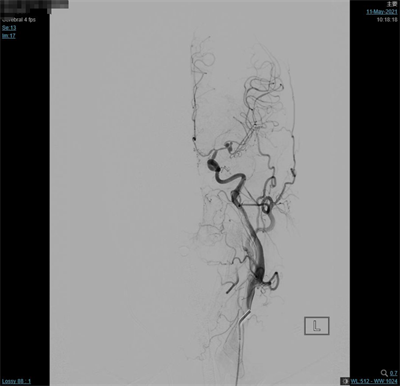

脑动脉造影(外院,2021-5-10):双侧大脑中动脉分叉多发动脉瘤。

夹闭前造影